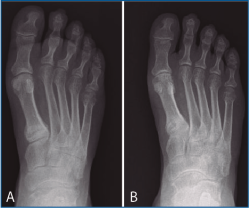

Figura 4. Caso 2. Fractura por estrés de la base del primer metatarsiano del pie derecho pasados 19 meses de la intervención (A). Consolidación de la fractura tras tratamiento ortopédico (B).